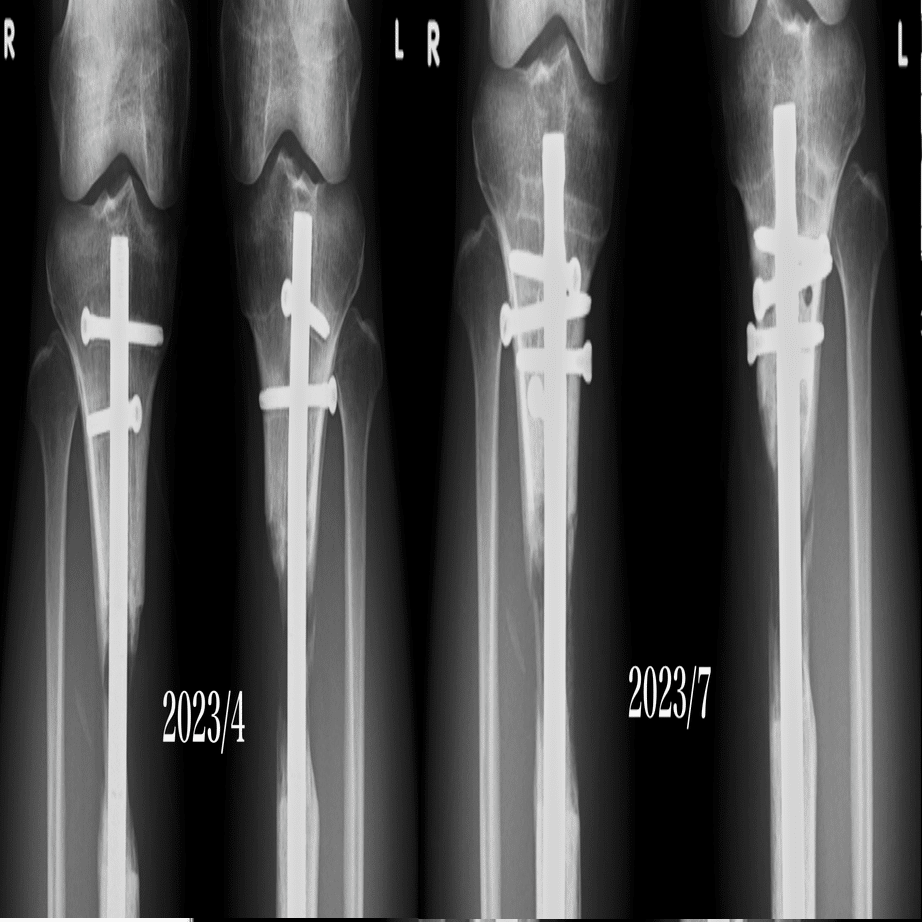

実験として左足にだけ試しに20日間ほど使用すると止まりかけの骨形成が復活してきました。

骨密度も増したような気がします。 pic.twitter.com/V7uFJoajW4